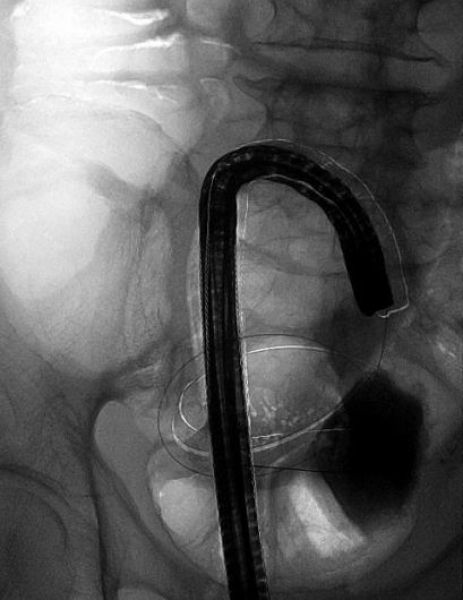

63岁男性田某,因肛门停止排气排便10余天拟肠梗阻收住消化二科。腹部CT提示肠梗阻、直肠乙状结肠占位,肠镜发现结肠距肛门19cm处有一新生物,管腔狭窄,活检提示低分化腺癌。根据病情,患者需行外科手术(一期造瘘,二期回纳),造瘘后需在腹壁挂着一个粪袋,既不便于生活,也不雅观,增加了病人的痛苦及经济负担。且该患者半年前因冠心病行了冠脉支架置入术,一直服用拜阿司匹林及氯吡格雷抗血小板药物,短期内不宜外科手术。经消化内科与普外科讨论后于4月23日在介入室成功置入肠道支架,肠道支架置入后即刻见粪便涌出,排气排便恢复。术后转外科行一期手术切除肿瘤。

肠镜下见结肠肿瘤 造影见肠腔狭窄,口侧肠管扩张

置入肠道支架